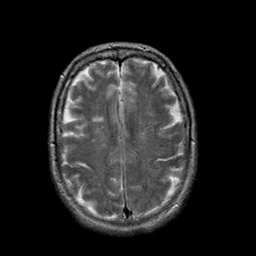

Stroke:T2-weighted MR #1 -- Slice #18

[Home][Help][Clinical] Slice 18